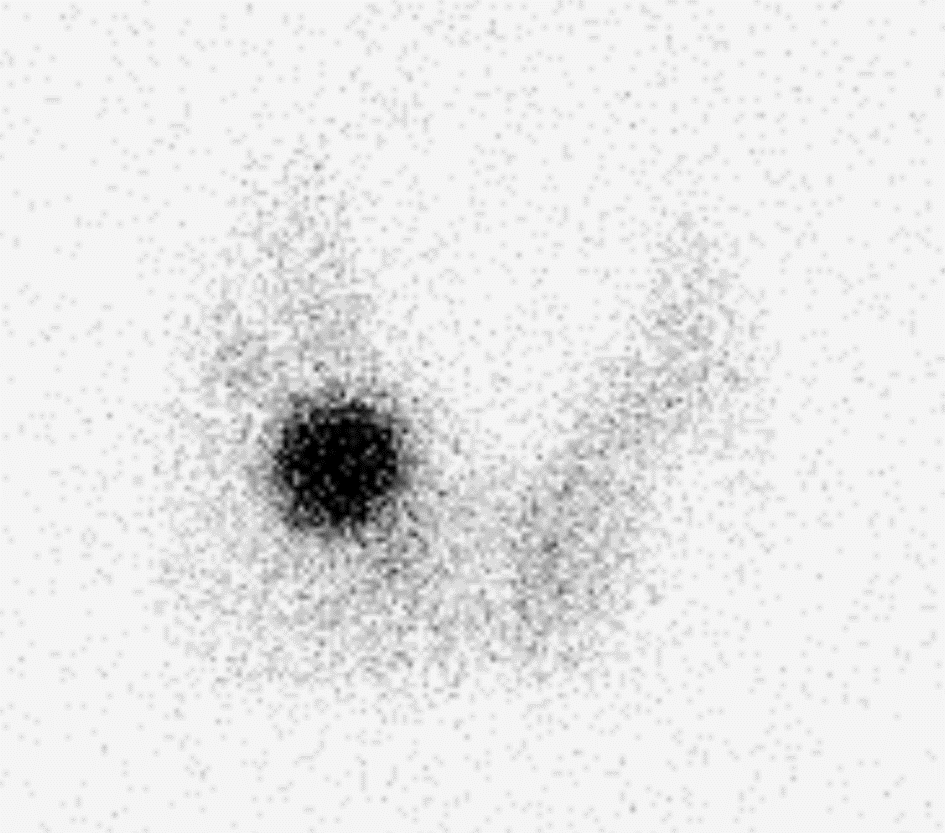

L’image ci-dessous est un exemple de résultats obtenu en scintigraphie thyroïdienne. La zone apparaissant en noir correspond à une région de la thyroïde fonctionnant de façon trop importante.